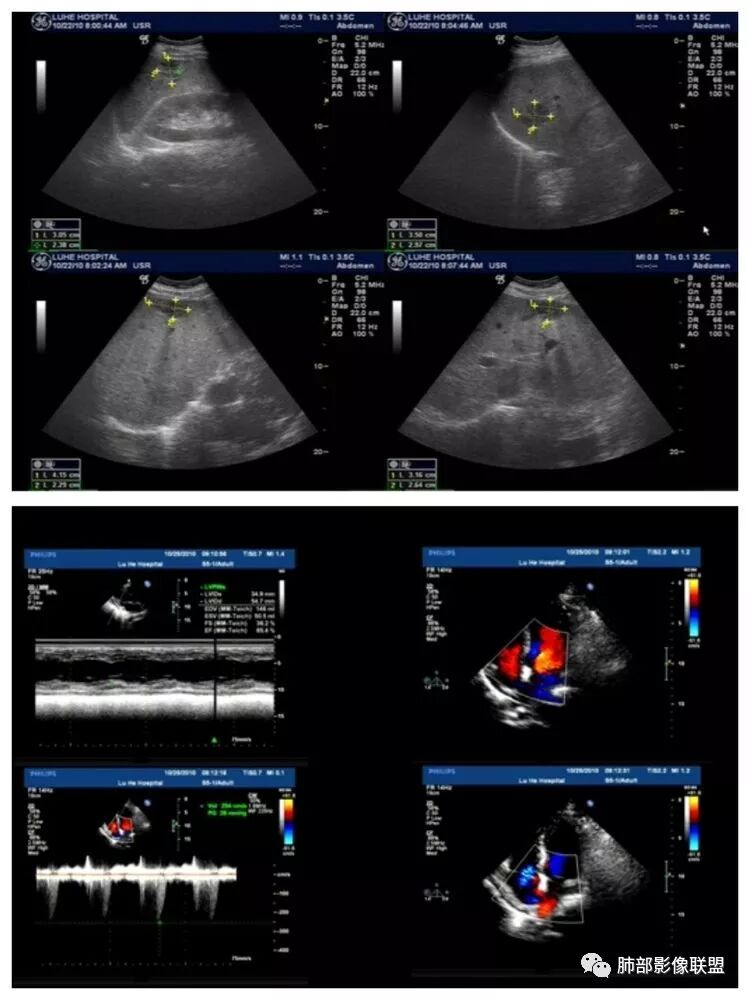

腹部B超及心脏彩超

脾大,肝内结节中央似有点状血管通过,炎性可能

4.本例肝脏的病灶并未出现典型肝脓肿图像特征,病灶密度及中央血管样结构显然不符合一般的囊肿。应当说,它是感染灶,但并未液化形成脓腔。